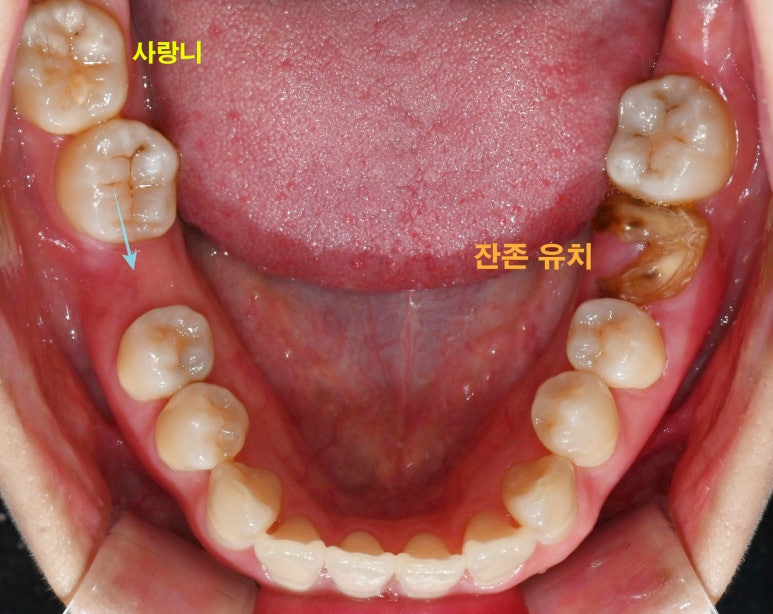

하악도 마찬가지로

사랑니가 존재하고,

여기서 주목해야 될 것은 바로

만기 잔존해 있는 치아입니다.

왼쪽 아래 부러진 채로 남아있는

유치가 있으며

오른쪽은 언제 빠졌는지는 모르나

이가 빠진 채로 시간이 지나면서

그 뒤 어금니가 앞으로 기울어져

공간이 좁아져있습니다.